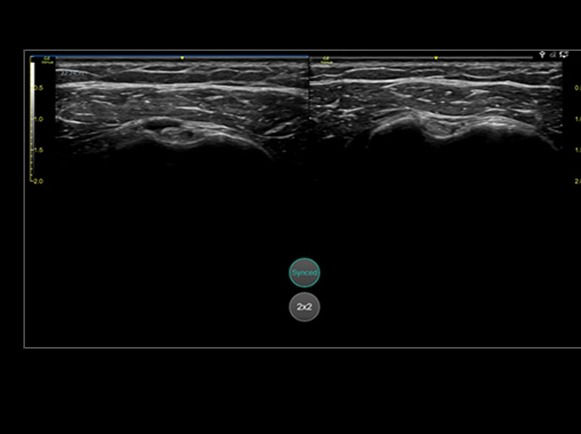

• Bilateral mode: Helps you to view the opposite side of the same zone for comparison (available for Shoulder preset)